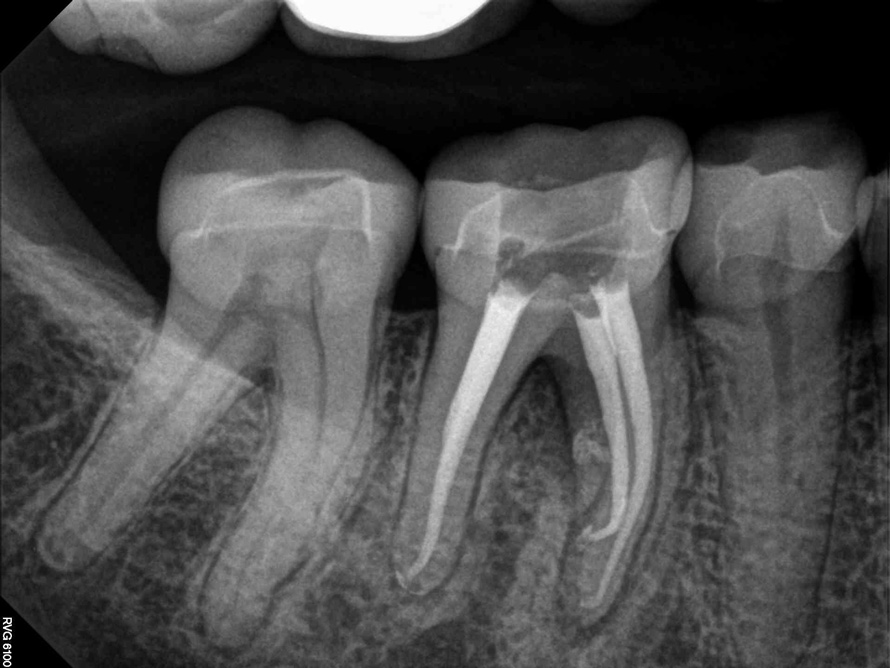

Fig 7. Cases treated by the continuous wave of condensation technique using gutta percha and epoxy resin sealer.

Figure 7

Fig 8. Cases treated by the continuous wave of condensation technique using gutta percha and epoxy resin sealer.

Figure 8

A version of warm vertical compaction, termed the continuous wave of condensation, is one of the most widely utilized obturation techniques19 (Figure 7 and Figure 8). This method involves placement of a single, tapered gutta percha cone fit to the same size as the master apical file with sealer, and downpacked with a controlled electric heat source. Based on the rotary instrumentation system used, either 04 or 06 tapered, ISO standardized apical size gutta percha cones corresponding to the final size and shape of the prepared canal can be placed with an appropriate sealer. A plugger heated to 200°F is introduced into the apical third of the root as determined by the working length to condense the apical portion of gutta percha. The heating element is turned off but left in place for an additional 5 seconds to allow slight cooling before a quick burst of heat. The heating element is removed with the coronal portion of excess gutta percha. Following this, the remainder of the canal space is filled using flowable gutta percha delivered via a motorized backfill device to the level of the chamber floor. This method can be hybridized with lateral compaction, in which spreaders are used to add accessory cones, when the shape of the canal does not allow for a tight fit of the ISO sizes of gutta percha points.